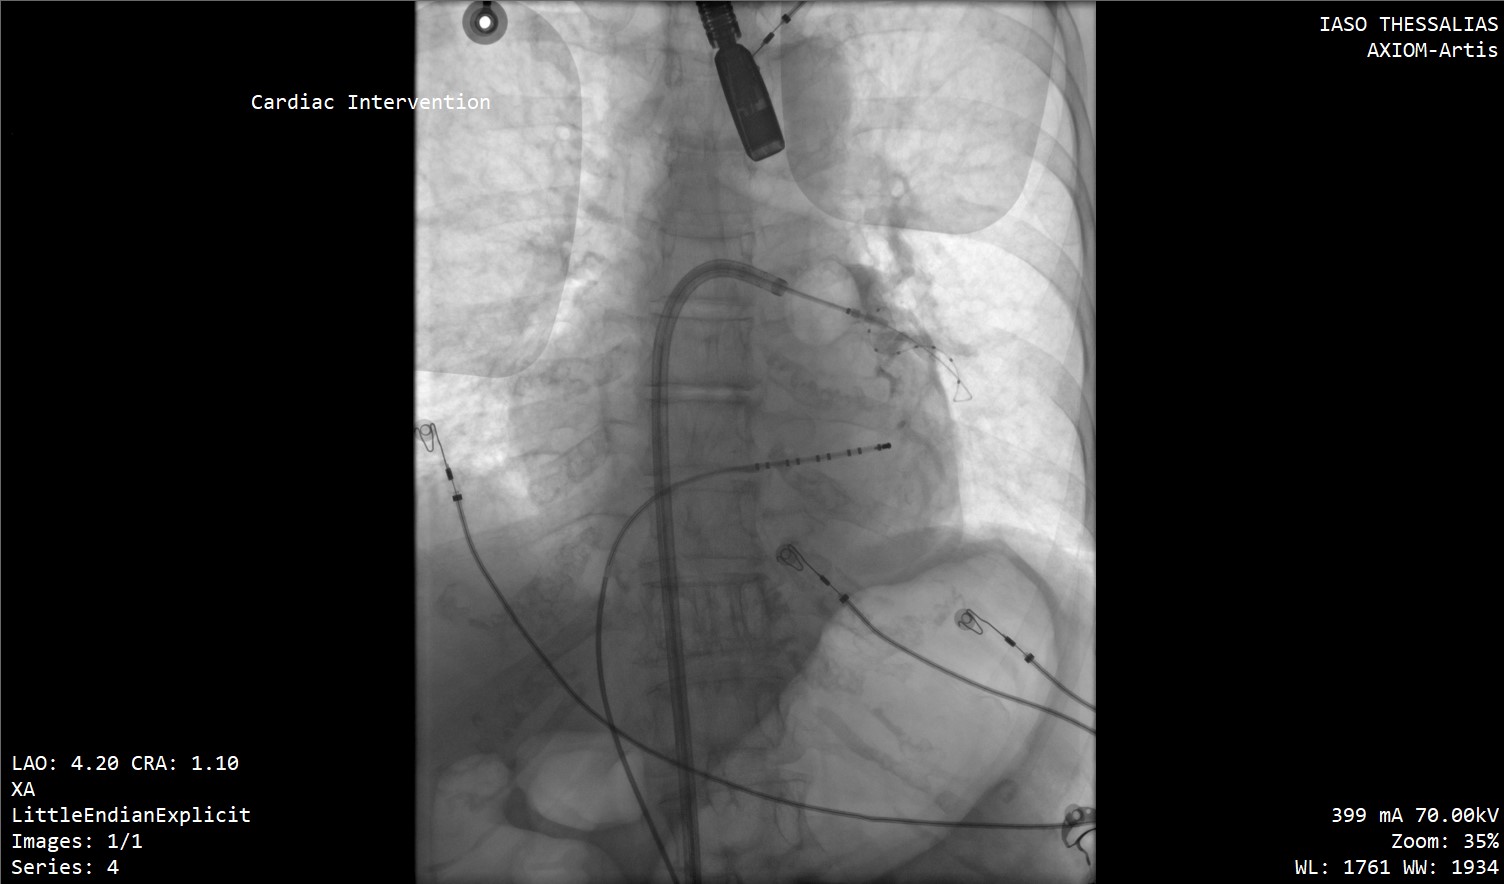

Μια νέα εποχή στην αντιμετώπιση των καρδιακών αρρυθμιών εγκαινιάζεται στην Κεντρική Ελλάδα, καθώς οι πρώτες επεμβάσεις κατάλυσης με καθετήρες (ablation) για τη θεραπεία της κολπικής μαρμαρυγής πραγματοποιήθηκαν με απόλυτη επιτυχία στο ΙΑΣΩ Θεσσαλίας.

Οι επεμβάσεις διενεργήθηκαν από τον Επεμβατικό Ηλεκτροφυσιολόγο Δημήτριο Α. Ιατρόπουλο, σε συνεργασία με τον Αναισθησιολόγο Δήμο Χαραλαμπίδη, τον Καρδιολόγο Αργύρη Γκαρμπούνη και την άρτια εκπαιδευμένη ομάδα του τεχνολογικού και νοσηλευτικού προσωπικού του Αιμοδυναμικού Εργαστηρίου του ΙΑΣΩ Θεσσαλίας.

Στις συγκεκριμένες επεμβάσεις εφαρμόστηκε η σύγχρονη τεχνική κρυοκατάλυσης με τη χρήση ειδικού μπαλονιού κρυοπηξίας (Cryoballoon), το οποίο επιτρέπει την ελεγχόμενη ψύξη («πάγωμα») του καρδιακού ιστού γύρω από τις πνευμονικές φλέβες, επιτυγχάνοντας με ασφάλεια και ακρίβεια την ηλεκτρική τους απομόνωση. Η μέθοδος χαρακτηρίζεται από υψηλά ποσοστά επιτυχίας, μειωμένο χρόνο επέμβασης και ταχεία ανάρρωση των ασθενών.